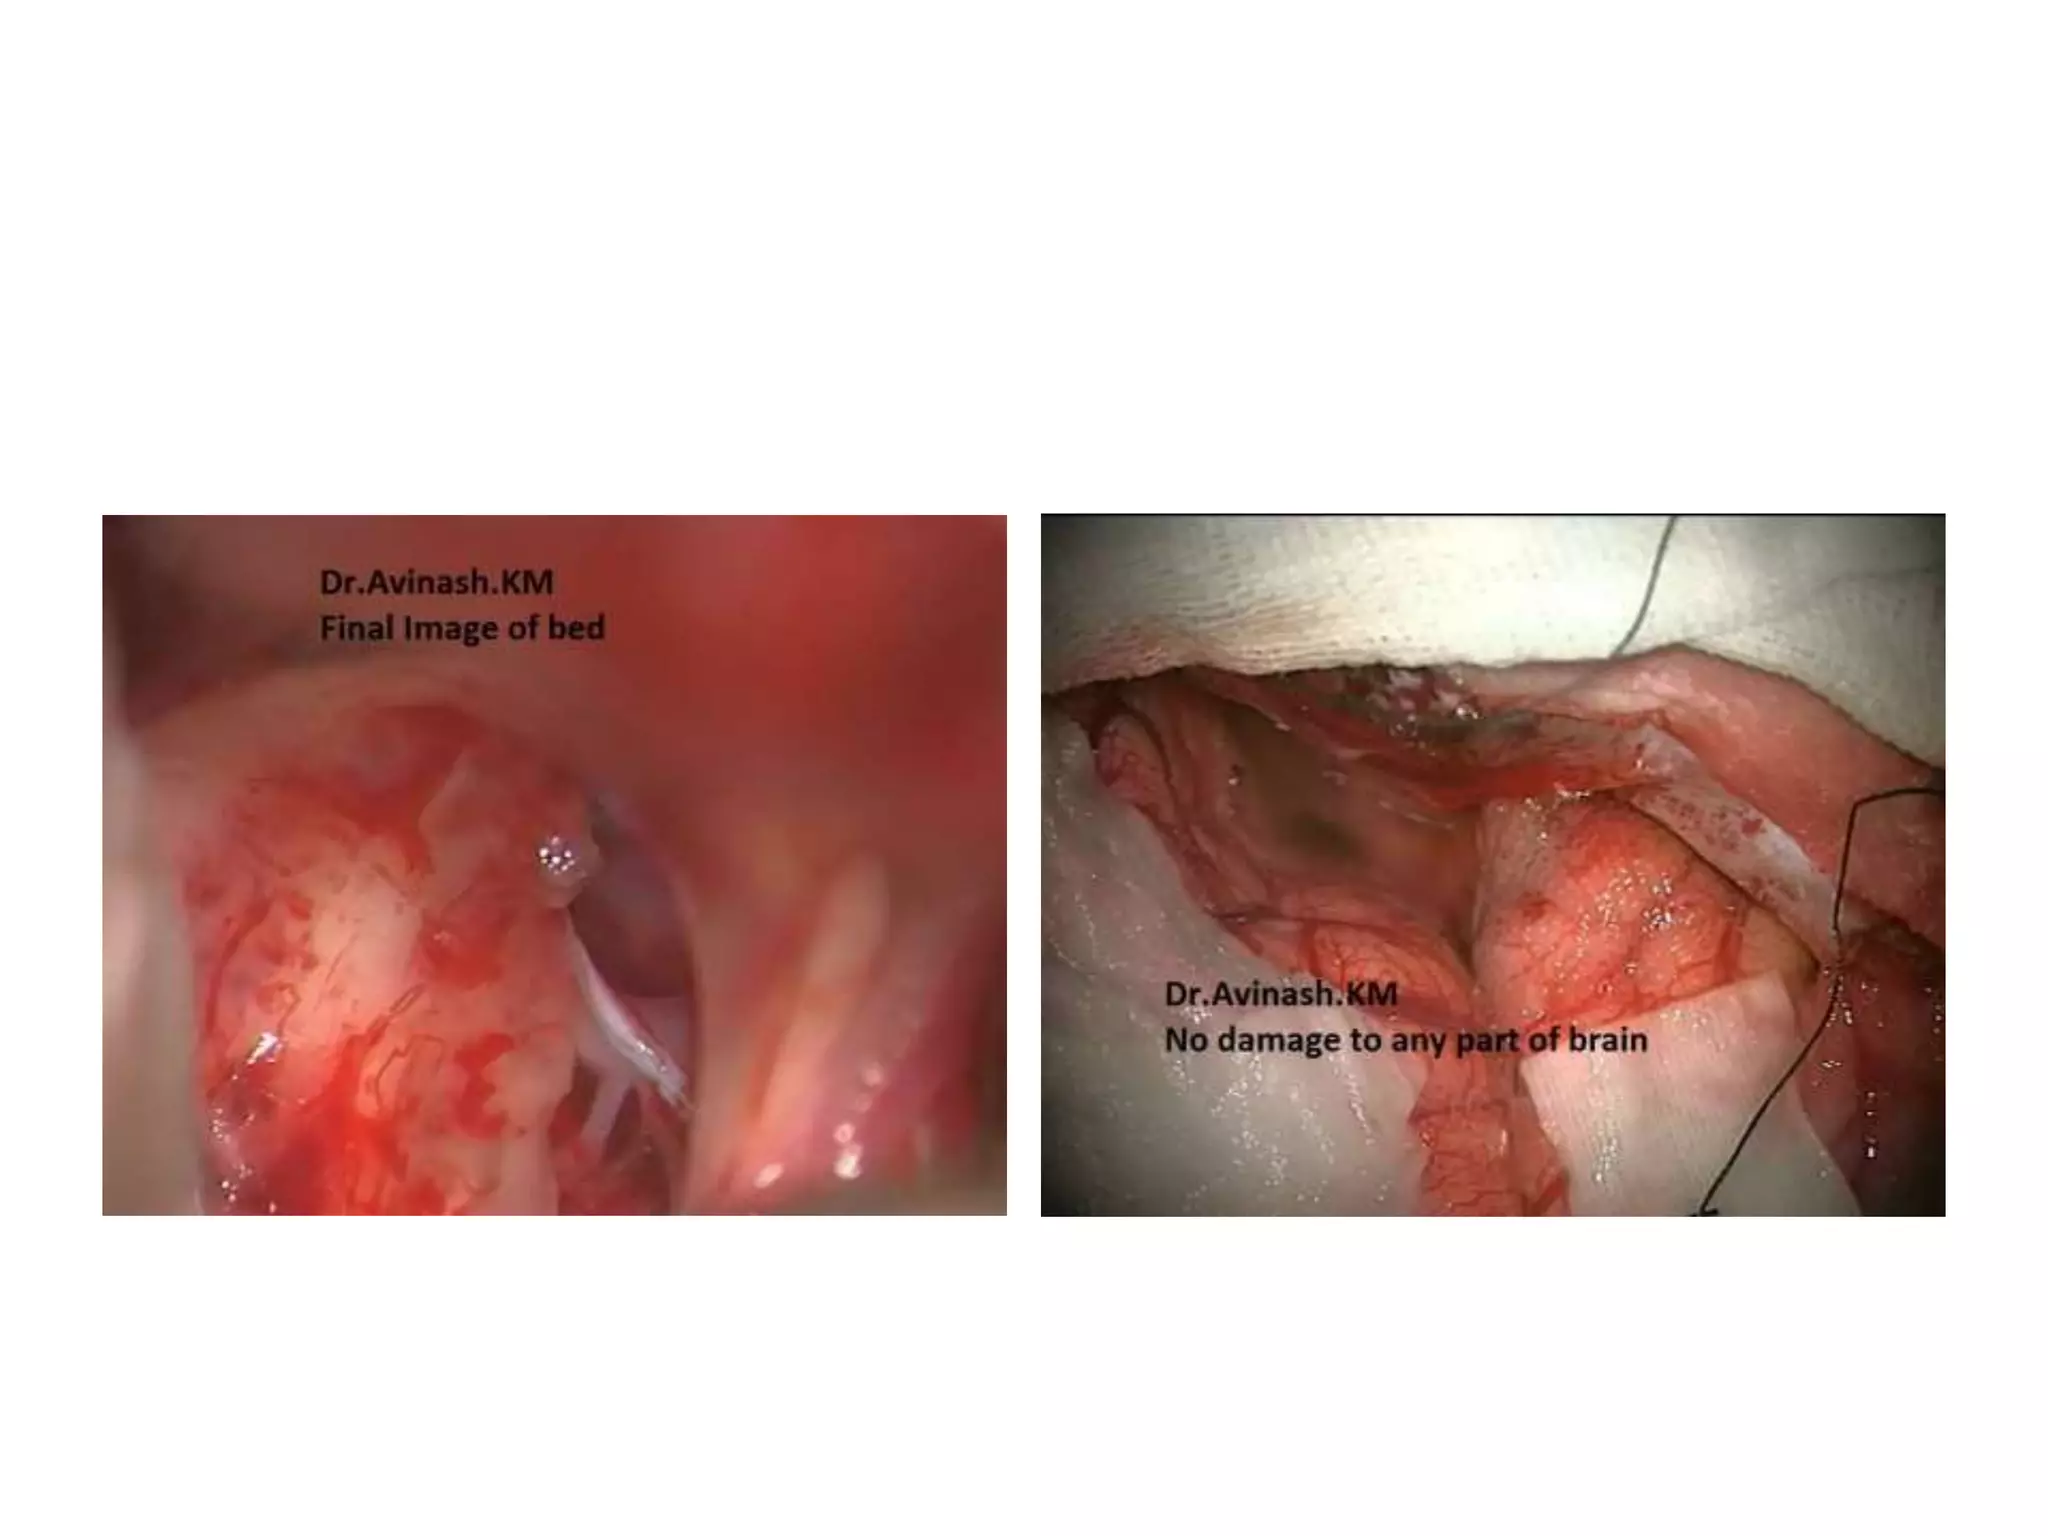

Craniopharyngioma

CRANIOPHARYNGIOMAS-Removal corridors.